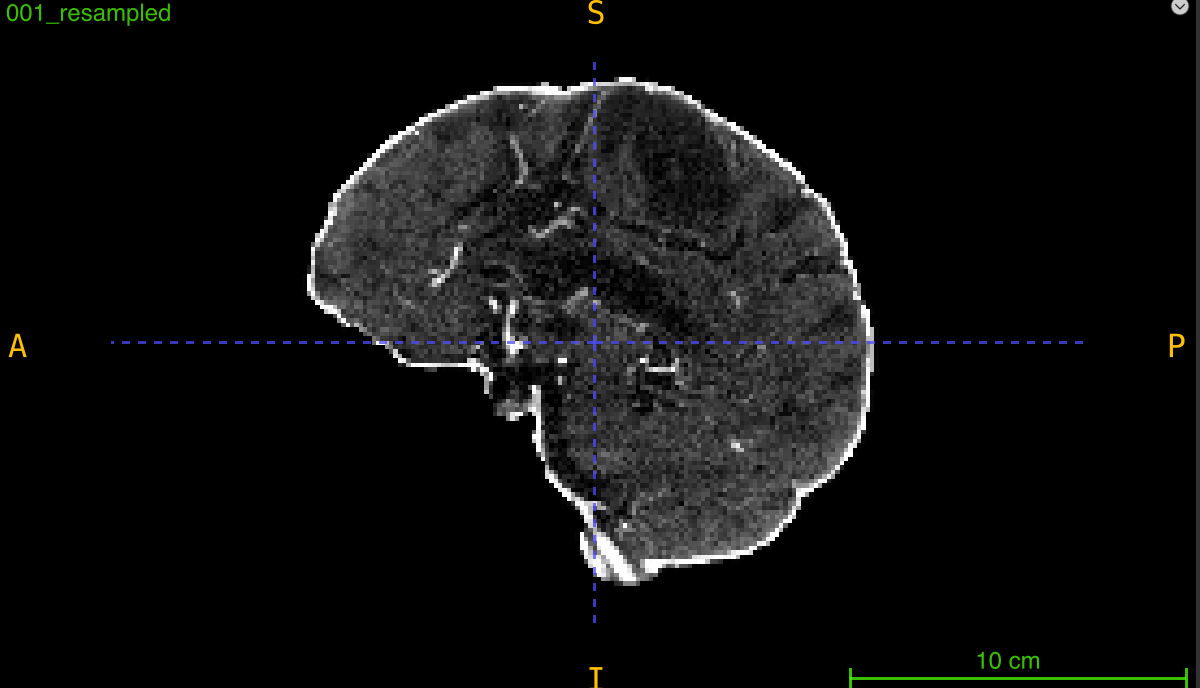

Comparing Interpolation Quality

Visualize resampling results:

import nibabel as nib

import matplotlib.pyplot as plt

from nidataset.preprocessing import resampling

# Resample

resampling(

nii_path="visualization/scan.nii.gz",

output_path="visualization/resampled/",

desired_volume=(224, 224, 128),

debug=True

)

# Load and compare

original = nib.load("visualization/scan.nii.gz")

resampled = nib.load("visualization/resampled/scan_resampled.nii.gz")

orig_data = original.get_fdata()

resamp_data = resampled.get_fdata()

# Extract middle slices

orig_mid = orig_data.shape[2] // 2

resamp_mid = resamp_data.shape[2] // 2

fig, axes = plt.subplots(1, 2, figsize=(12, 5))

axes[0].imshow(orig_data[:, :, orig_mid], cmap='gray')

axes[0].set_title(f'Original ({orig_data.shape})')

axes[0].axis('off')

axes[1].imshow(resamp_data[:, :, resamp_mid], cmap='gray')

axes[1].set_title(f'Resampled ({resamp_data.shape})')

axes[1].axis('off')

plt.tight_layout()

plt.savefig('resampling_comparison.png', dpi=150)

print("Comparison saved: resampling_comparison.png")